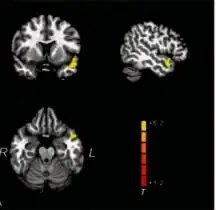

| Brain regions where there were significant reductions in the gray matter volume in right-side unilateral sudden sensorineural hearing loss individuals relative to healthy controls | |